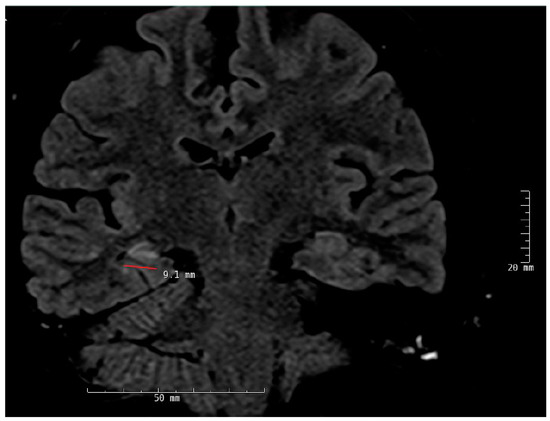

4.2.1. MRI (Magnetic Resonance Imaging)

- Dredla, B.K.; Lucas, J.A.; Wharen, R.E.; Tatum, W.O. Neurocognitive outcome following stereotactic laser ablation in two patients with MRI-/PET+ mTLE. Epilepsy Behav. 2016, 56, 44–47. [Google Scholar] [CrossRef] [PubMed]